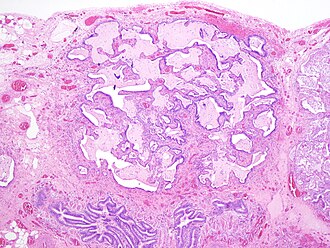

Fibroblast focus in usual interstitial pneumonia. H&E stain. | |

| LM | fibroblast foci, interstitial inflammation, microscopic honeycombing (typically peripheral & lined by ciliated epithelium), spatial heterogeneity - patchy lesional distribution (areas of abnormal and normal lung may appear beside one another), temporal heterogeneity - lesions of differing age side-by-side |

Microscopic

Features:[6]

- Fibroblast foci:

- Interstitial inflammation.

- Microscopic honeycombing.

- Typically peripheral - cysts lined by ciliated epithelium.

- Spatial heterogeneity - patchy lesional distribution (areas of abnormal and normal lung may appear beside one another).

- Temporal heterogeneity - lesions of differing age side-by-side.[9]